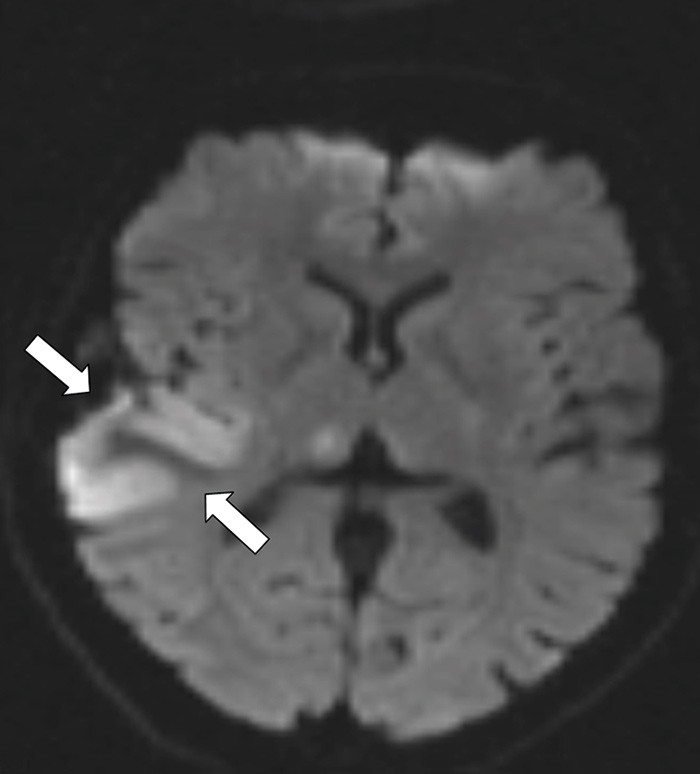

A previously healthy woman in her 40s suffered morning headache and vomiting the day before admission. She was a non-smoker and used no medicines or hormones. On the following day she developed acute left facial paresis, left arm paresis and dysarthria. She experienced transient spasms in the left part of her face. Cerebral CT performed at the local hospital showed a high-attenuation lesion in the right temporoparietal lobe (see online version for picture). D-dimer was 0.8 mg/l (normal < 0.4). A vascular event in the right hemisphere was suspected. Cerebral MR venography at the university hospital the following day revealed an intraluminal venous thrombus corresponding to the right vein of Trolard (left picture). Diffusion-weighted cerebral MRI showed a mix of vasogenous and cytotoxic oedema in the temporoparietal region, typical of a venous infarction (right picture). Tests of thrombocoagulation system function revealed activated protein C resistance 0.66 (normal 0.85 – 1.15). The patient received anticoagulant therapy and six days later follow-up cerebral MR venography showed normalisation. She was discharged without sequelae.

Cerebral venous thrombosis often presents with severe headache and may cause focal neurological impairment and epileptic attacks in the presence of an infarction. Activated protein C resistance predisposes for cerebral venous thrombosis, which is a rare (0.5 – 1 %) cause of cerebral infarction (1). Early diagnosis and treatment are essential for a good clinical outcome. CT and MR venography enable non-invasive visualisation of venous cerebral thrombosis with a high degree of sensitivity and specificity.